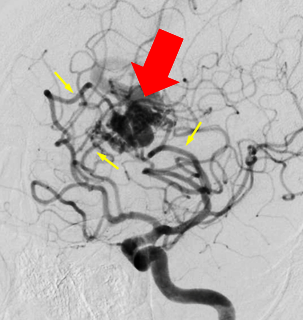

Angiography:

- CMs are typically angiographically occult (no

nidus, no early venous drainage).